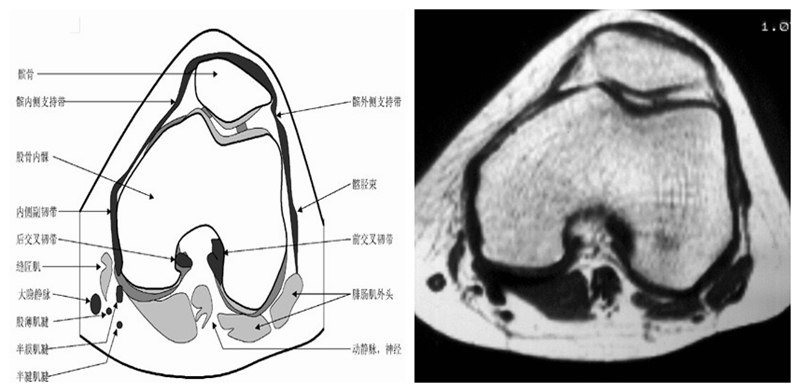

膝关节横断面MRI解剖

三维影像首选的方位,便于与CT比较,可准确地展现髌骨内外侧关节面。

横断面解剖第二层